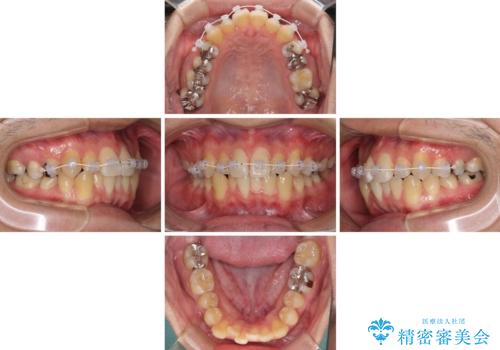

- 矯正装置

- インビザライン

- 治療期間

- 1年3ヶ月

前歯を早く整えたいとの希望があったので、ワイヤー矯正にて短期間でクロスバイトを解消し、その後インビザラインにて整えることとしました。

インビザラインによる前歯のクロスバイト改善におけるリスクとして、前歯歯髄充血・歯髄壊死が挙げられます。

ワイヤー矯正を併用する目的として、短期間でデコボコやクロスバイトを改善する他に、歯髄充血リスクを低減させるというものがあります。